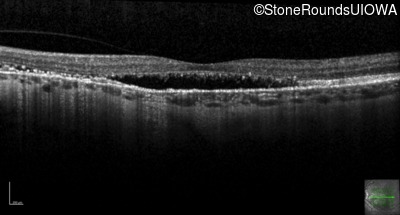

Optical Coherence Tomography - Right - 20/20 -3 sc

Exemplar / OCT Stack

OCT Stack